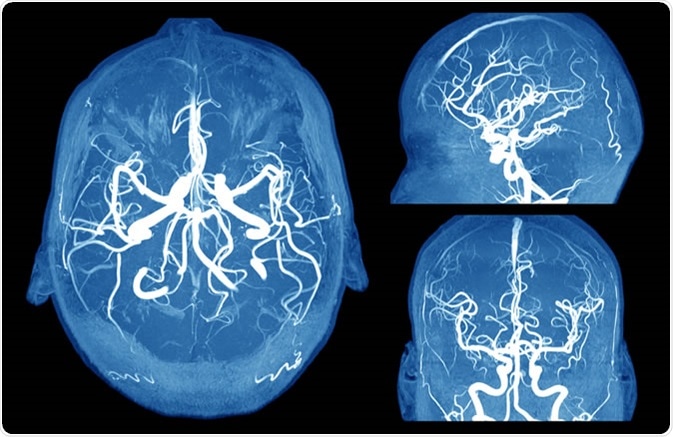

Brain aneurysm MRI. Image Credit: MriMan / Shutterstock